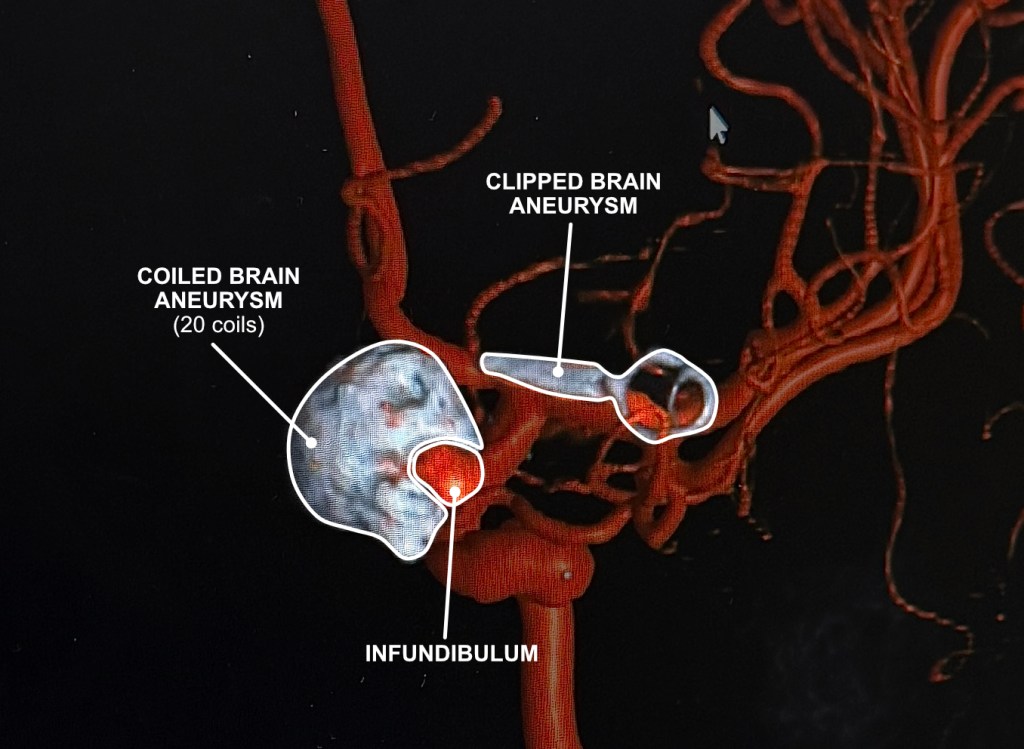

I was able to grab a screen capture of the latest angiogram images in the doctor’s office. Really fascinating to see the large 11mm original aneurysm filled with coils showing as a large gray mass. Then to see how close the clip actually is to the first aneurysm. As Dr. Ecker said, neurologically speaking “it’s in another room.” due to the microscopic aspect of their work. He also pointed out where the infundibulum is. It looks big to me, but it’s only around 3.7mm.